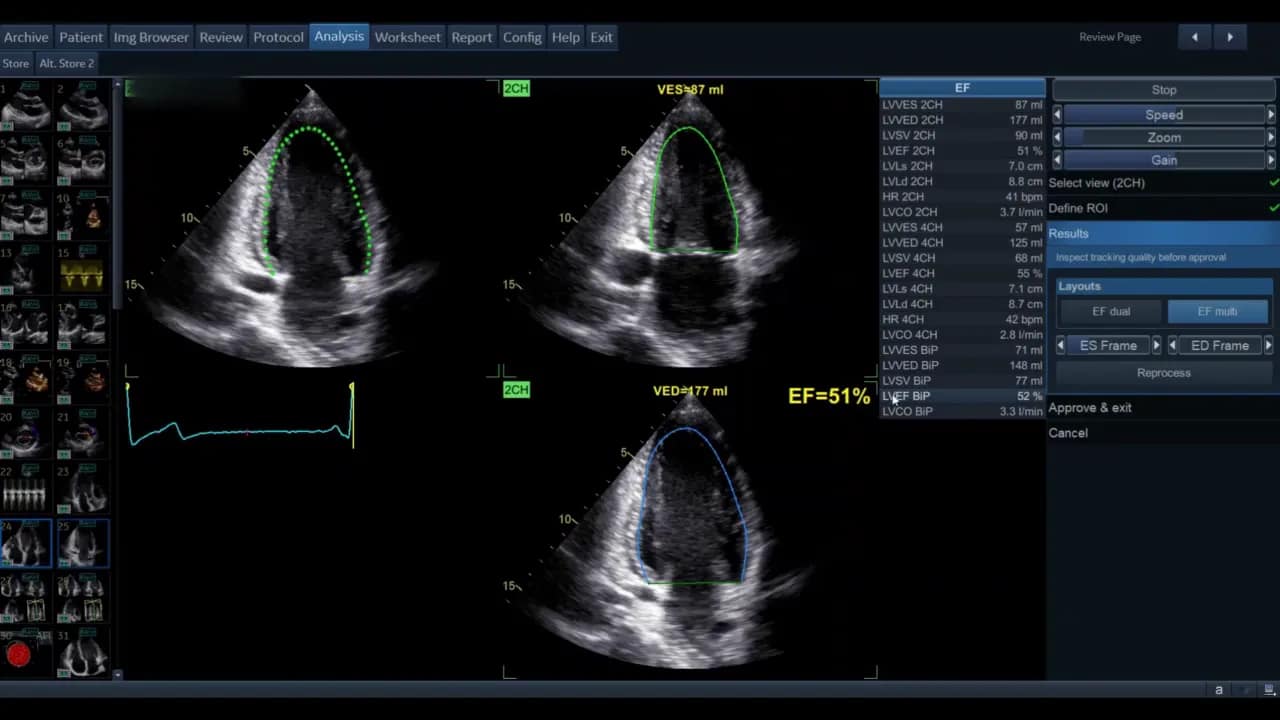

Die Ansicht kann als Einzelbild oder als EF‑Dual‑Display gezeigt werden. Im Dual‑Display sehen Sie gleichzeitig Systole und Diastole mit den berechneten Volumina und der Ejektionsfraktion als Prozentsatz.

Die Software zeigt nach erfolgreichem Durchlauf die systolischen und diastolischen Volumina beider Ansichten sowie die berechnete biplane Ejektionsfraktion. Diese Werte erscheinen in der Ergebnisliste; die biplane EF wird in der Regel als kombinierter Wert ausgewiesen.

Die AutoEF liefert Volumina für EDV (end‑diastolic volume) und ESV (end‑systolic volume) sowie die EF. Interpretieren Sie die Werte im klinischen Zusammenhang: